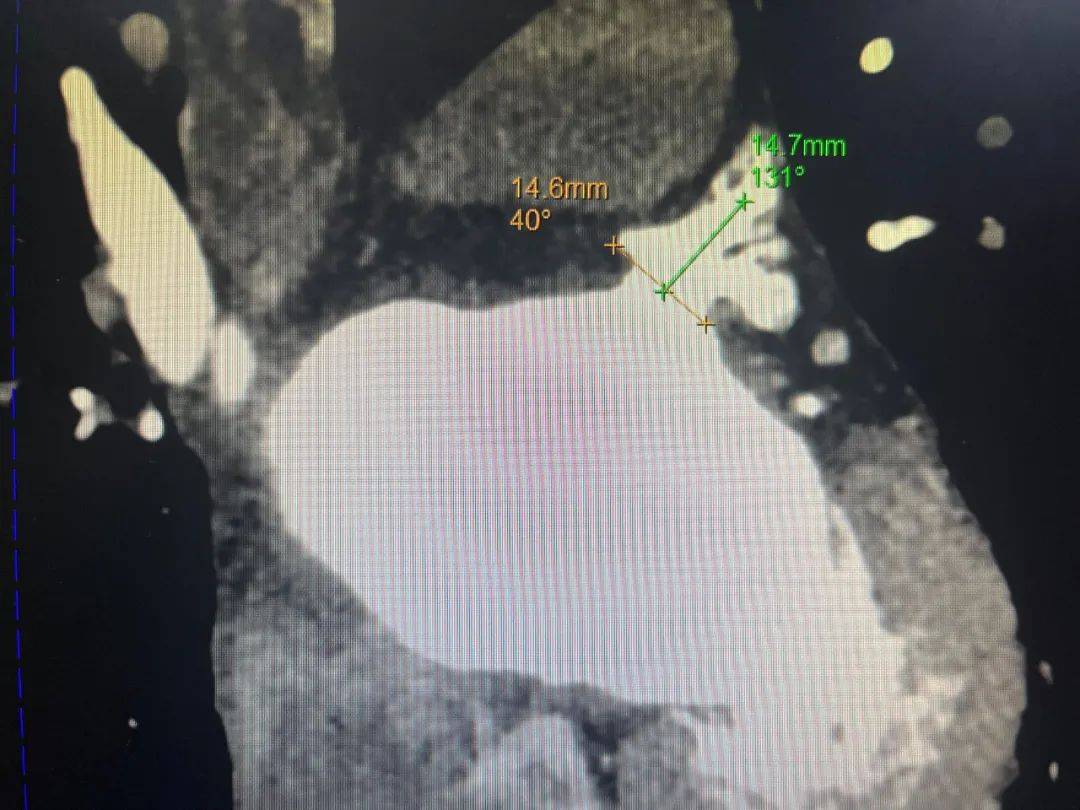

左心耳cta测量